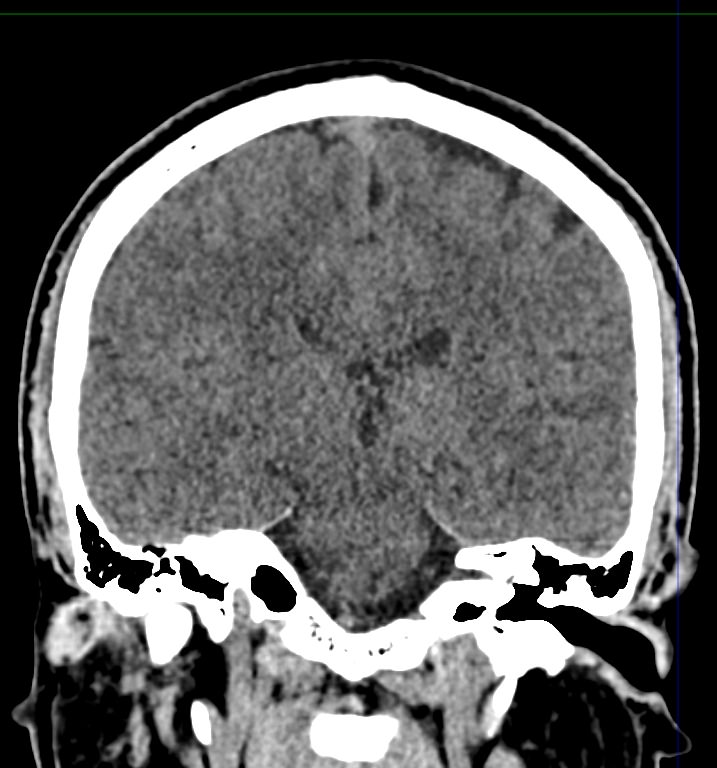

Мультиспиральная компьютерная томография головного мозга относится к лучевым методам диагностики заболеваний центральной нервной системы.

Методика построена на использовании проникающей способности рентгеновских лучей, которые в различной степени поглощаются органами и тканями (степень поглощения зависит от их плотности), благодаря чему можно получить подробные изображения внутренних органов. Во время исследования трубка томографа вращается вокруг пациента и производит снимки поперечного сечения, что позволяет детально визуализировать кости черепа и все структуры головного мозга.

Наши медицинские центры оснащены новейшими мультиспиральными компьютерными томографами экспертного уровня TOSHIBA AQUILION в различных модификациях. Аппараты снабжены увеличенным количеством сверхчувствительных детекторов, что позволяет при сканировании выполнять от 64 до 128 срезов поперечного сечения с минимальной толщиной среза от 0,5 мм. В результате получаются изображения исследуемой зоны в мельчайших подробностях, которые затем с помощью инновационных цифровых приложений преобразуются в трехмерные пространственные модели головного мозга для более точной диагностики.

Нативное сканирование подходит для диагностики дистрофических изменений головного мозга, определение острого нарушения мозгового кровообращения, как ишемического, так и геморрагического характера, а также отслеживание последствий подобных состояний при прохождении реабилитации.

Для улучшения видимости внутричерепных структур применяется методика внутривенного болюсного контрастирования. Во время проведения КТ пациенту в вену вводится йодсодержащее контрастное вещество. Контраст с током крови попадает в патологически измененные участки ткани и очаги, что на снимках придает им яркие отличительные признаки по сравнению с окружающими здоровыми тканями. Контрастирование, в первую очередь, помогает в диагностике опухолевых процессов на ранних стадиях, когда лечение может дать наилучший эффект.

Что можно выявить на КТ головного мозга?

- нарушения мозгового кровообращения (имеются в виду как геморрагические, так и ишемические инсульты);

- опухоли как доброкачественные так и злокачественные

- смещение внутренних структур головного мозга.